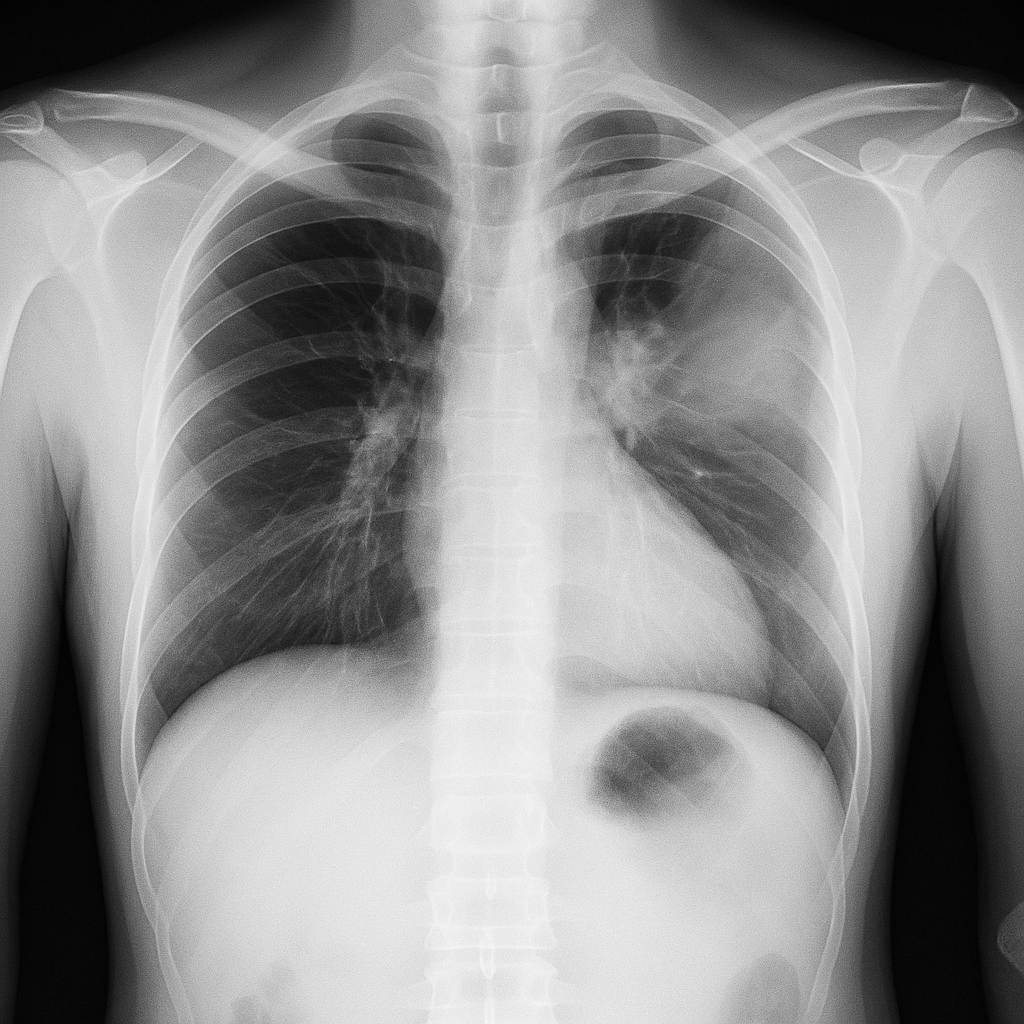

흉부 X-선 촬영이 기본적이고 효과적입니다.

증상과 진찰 소견으로도 진단을 의심할 수 있으며, 필요시 흉부 CT를 시행해 수술 여부 등을 판단합니다.